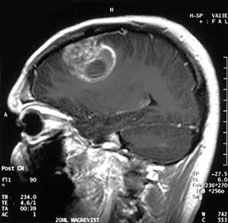

Credit: Image courtesy of A. Christaras/UC San Diego

The findings, published in the online October 13 issue of Cancer Cell, also present a potential alternative method for treating glioblastomas (GBM), the most common and most aggressive form of brain cancer. GBMs are extremely difficult to treat. The median survival rate is just over 14 months, with few treated patients living five years or more past diagnosis.